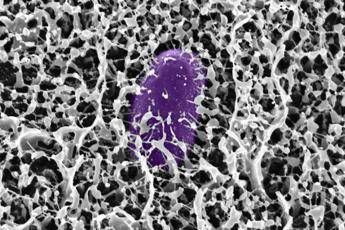

(Adnkronos) – Individuato il meccanismo d’azione delle mucine MUC2 contro i patogeni intestinali. La ricerca apre la strada allo sviluppo di farmaci sintetici per prevenire la “diarrea del viaggiatore”

Scoperta del MIT: il muco contiene molecole che bloccano l’infezione da Salmonella